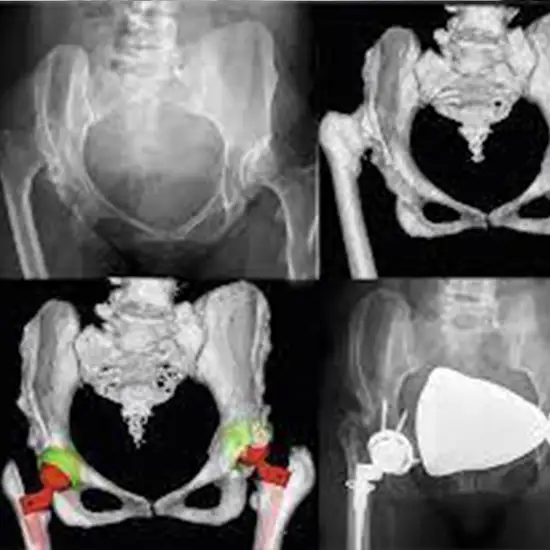

3D CT Hip Joint is an imaging scan to visualize hip joint in 3D reconstruction.

You need to lie supine on the CT table and scan is performed in the craniocaudal direction then the image is reconstructed in 3D view.